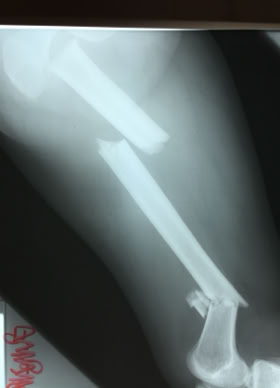

Traumatología

Coste del material de Osteósíntesis para una fractura de fémur

Gracias a COEM es posible realizar una traumatología del siglo XXI en una comunidad que de otra forma solo tendría acceso a una medicina medieval